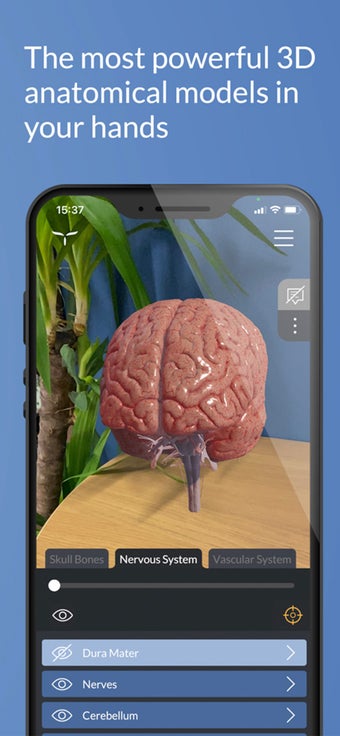

Además, el módulo "ARTouch" de esta aplicación te permite ver la neuroanatomía de manera híbrida utilizando el modelo físico AnatomyTouch.

De esta manera, puedes experimentar la belleza y precisión del modelo, lo que te permite estudiar y comprender el cerebro humano de una manera única y personal.